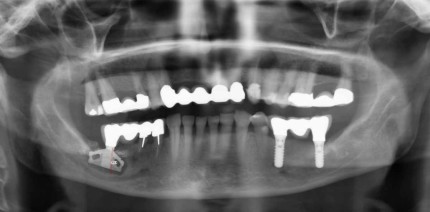

Bei dem damals 79-jährigen Patienten mussten 2018 nach der Abnahme der Kronen 15 bis 17 die Zähne wegen extremem Kariesbefall gezogen werden....

Bei dem damals 79-jährigen Patienten mussten 2018 nach der Abnahme der Kronen 15 bis 17...